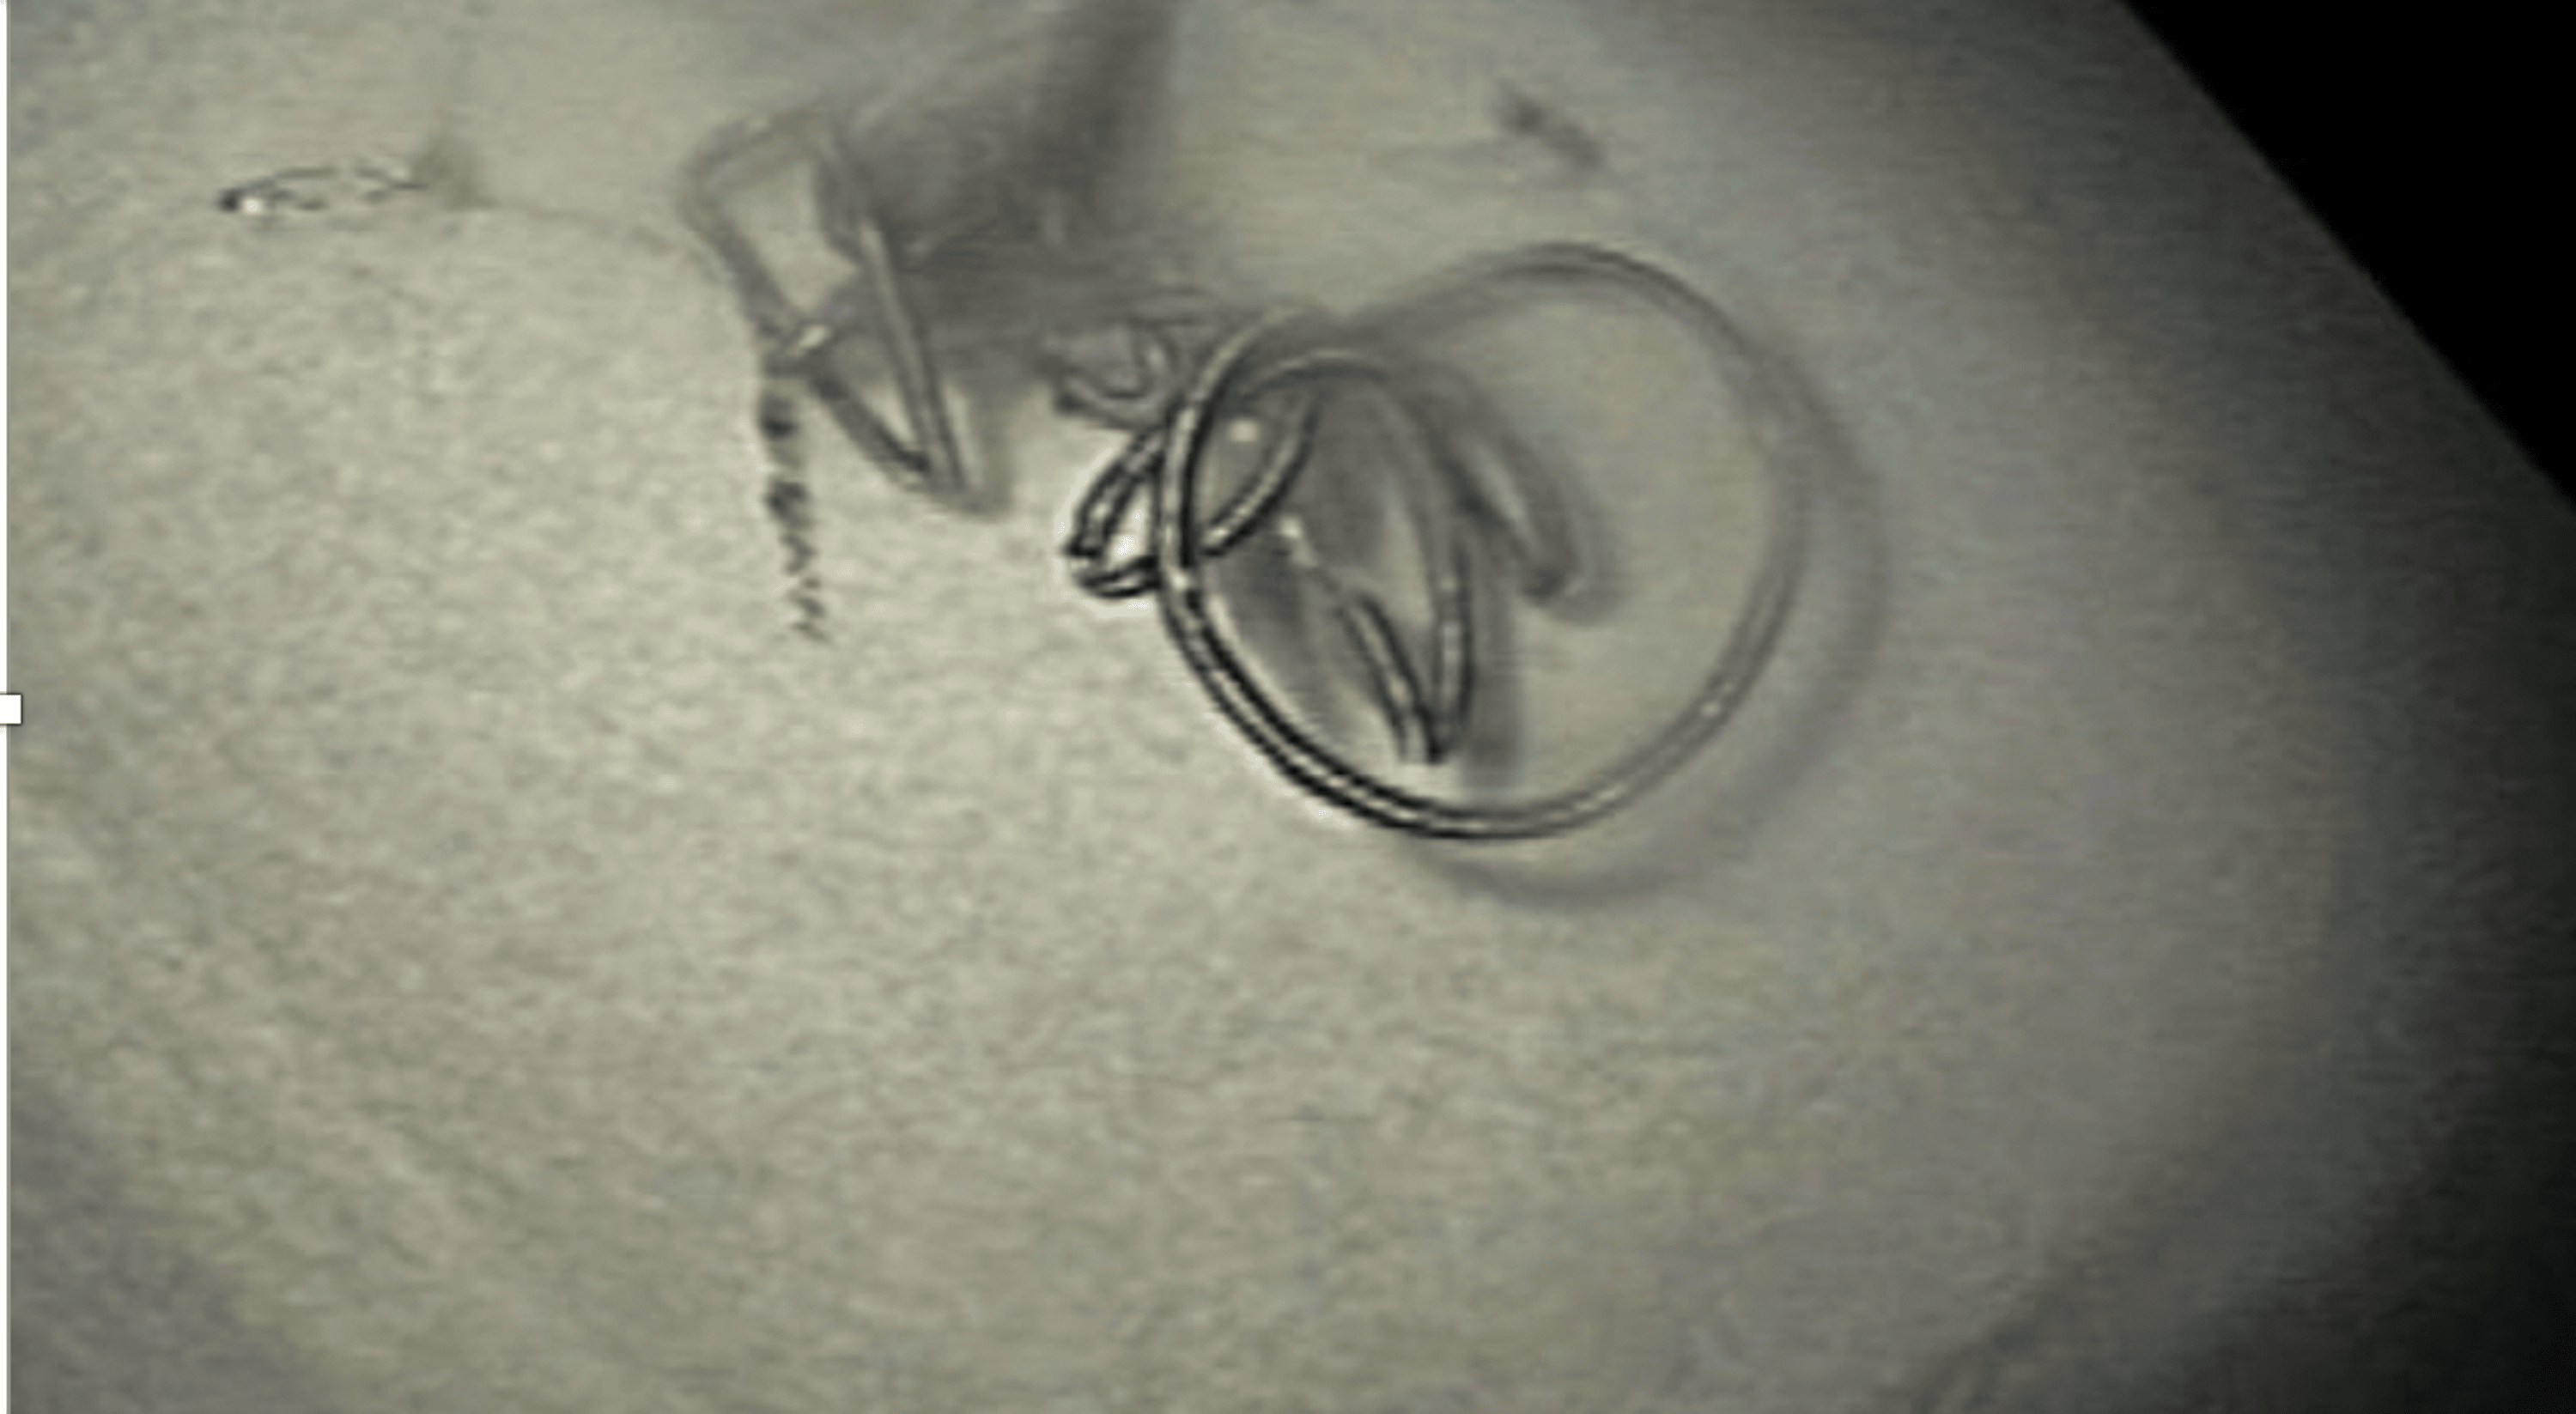

(A) Duodenal bulb with ulcer in sight. (B) Partially perforated coil Coil Embolization Duodenal Ulcer Endoscopic view of a large deep ulcer with a pulsatile visible vessel along the posterior aspect of the duodenal bulb. The primary clinical success rate was higher for duodenal ulcer (8 of 13 patients [62%]) and gastric cancer (3 of 5 patients. There is increased risk of gastric or duodenal infarction after embolotherapy in patients with previous extensive ugi surgery. Coil Embolization Duodenal Ulcer.

(PDF) Endoscopic View of Embolization Coil in a Duodenal Ulcer Coil Embolization Duodenal Ulcer Endoscopic view of a large deep ulcer with a pulsatile visible vessel along the posterior aspect of the duodenal bulb. There is increased risk of gastric or duodenal infarction after embolotherapy in patients with previous extensive ugi surgery or. The primary clinical success rate was higher for duodenal ulcer (8 of 13 patients [62%]) and gastric cancer (3 of 5. Coil Embolization Duodenal Ulcer.

Figure 1 from Endoscopic View of Embolization Coil in a Duodenal Ulcer Coil Embolization Duodenal Ulcer Endoscopic view of a large deep ulcer with a pulsatile visible vessel along the posterior aspect of the duodenal bulb. There is increased risk of gastric or duodenal infarction after embolotherapy in patients with previous extensive ugi surgery or. The primary clinical success rate was higher for duodenal ulcer (8 of 13 patients [62%]) and gastric cancer (3 of 5. Coil Embolization Duodenal Ulcer.